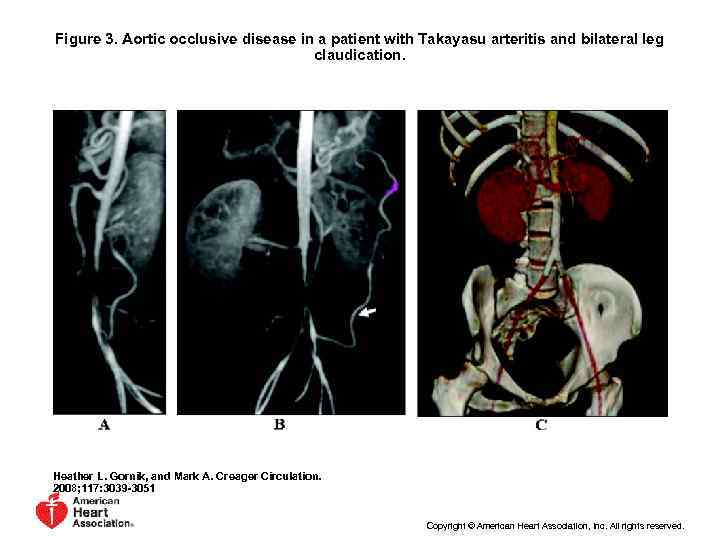

Figure 3. Aortic occlusive disease in a patient with Takayasu arteritis and bilateral leg claudication. Heather L. Gornik, and Mark A. Creager Circulation. 2008; 117: 3039 -3051 Copyright © American Heart Association, Inc. All rights reserved.